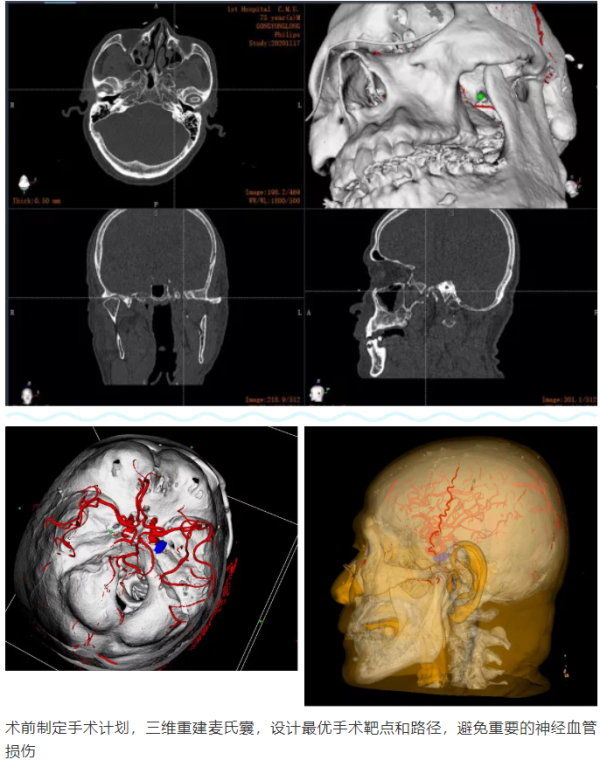

由于人体颅底结构复杂,骨质遮挡较多,传统徒手穿刺难度较大,即使穿刺成功也需不断调整进针方向找到卵圆孔的位置,有刺破颅底动脉血管的风险。而由机器人辅助的“经皮穿刺微球囊压迫术”,可以根据医生制定的手术规划,通过机器人的“脑”、“眼”、“手”精准定位至手术位置,由医生沿机械臂末端导向器穿刺到卵圆孔外口并植入微球囊压迫三叉神经半月节,术中影像验证植入微球囊位置是否准确。该术式创伤更小,术后患者疼痛立刻消失,避免了开颅手术可能致残、致死的风险,特别适用于无法耐受较长时间全麻及开颅手术等高龄、体弱或是具有严重系统疾病的三叉神经痛患者。